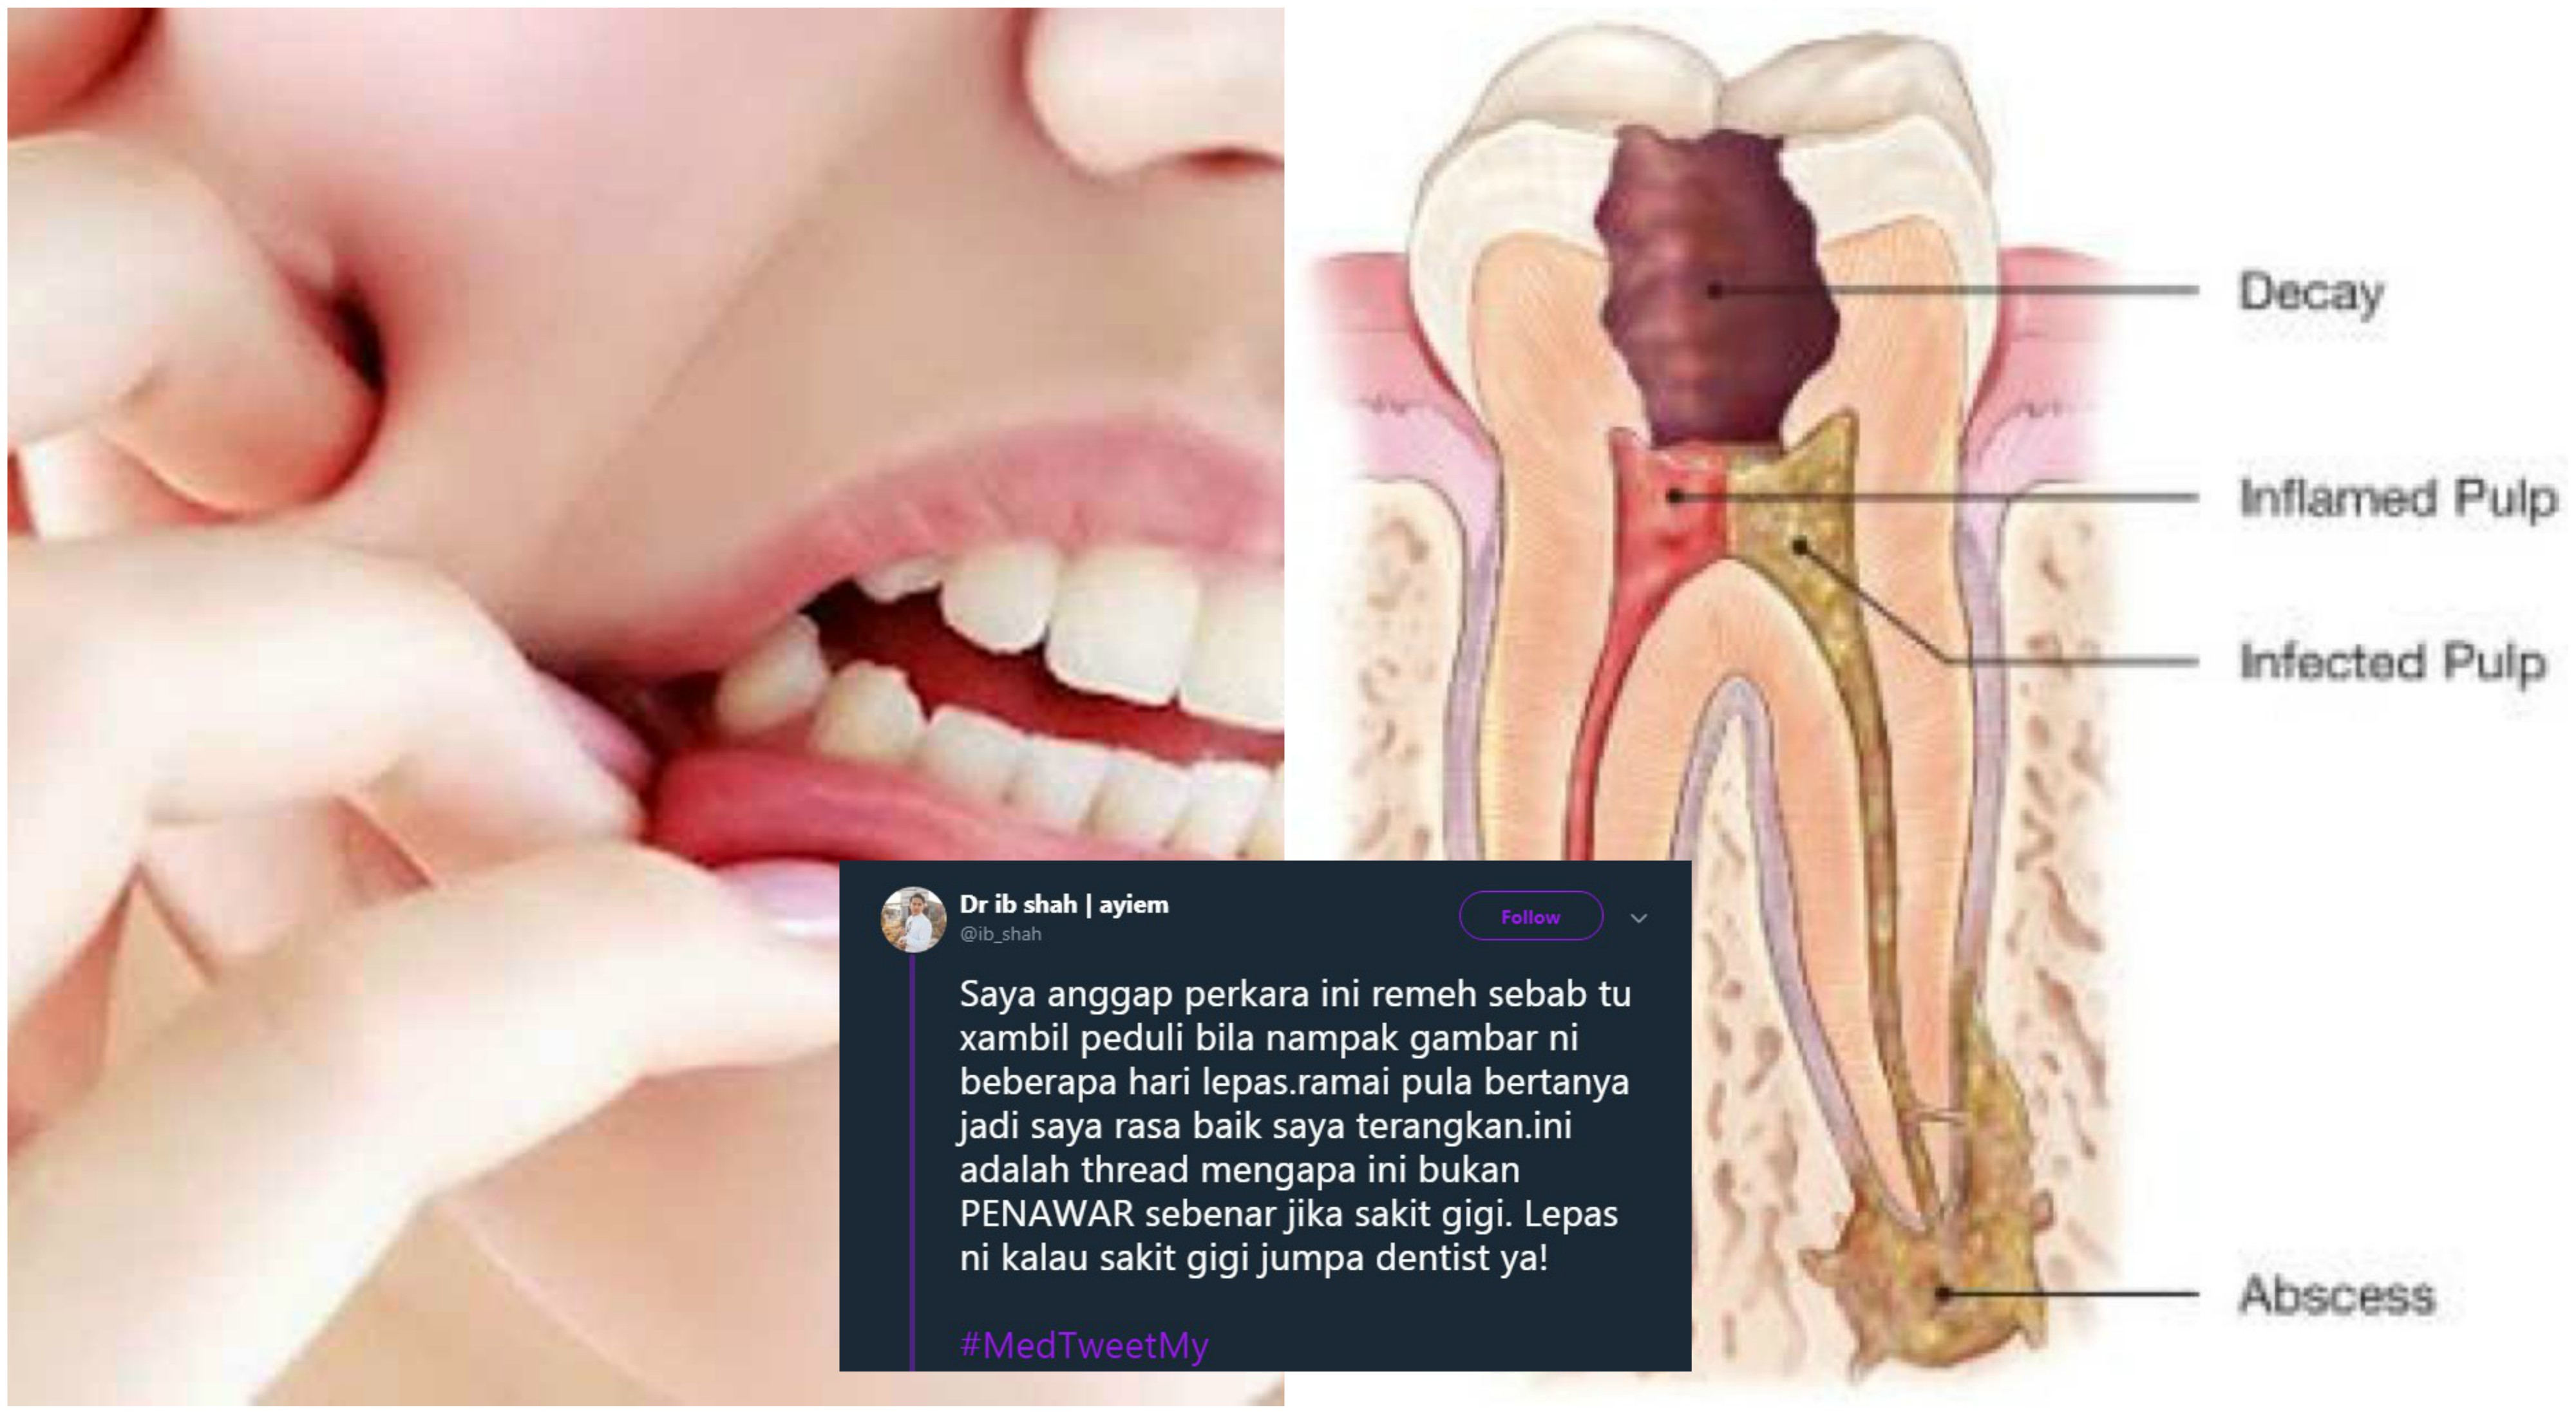

Gigi Bernanah Apa Yang Perlu Anda Tahu Dr Anis Ezrina The Malaysian Medical Gazette

Doktor Gigi Saya Belakang Sekali Sakit Sangat Kadang Kadang Gusi Bengkak Bila Bengkak Tu Nak Makan Pun Susah Buka Mulut Pun Susah